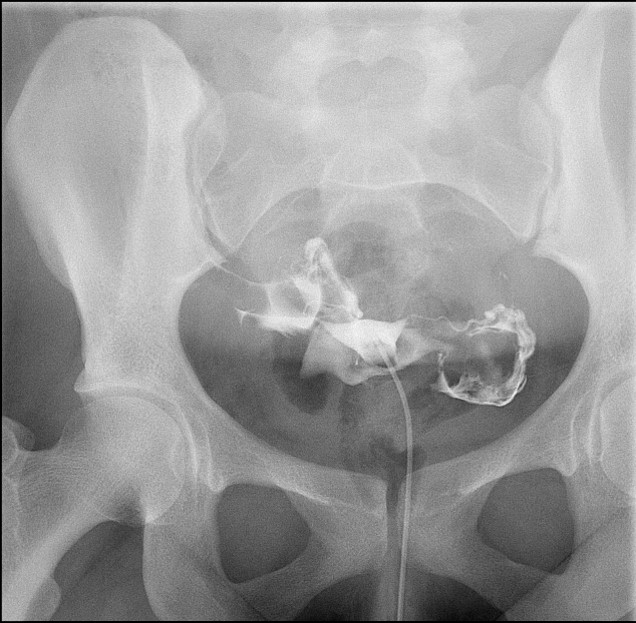

- When reviewing the preliminary scout film, you should see multiple surgical chain sutures in the pelvis

(key image 31)

(key image 32).

- After the enema tip has been placed but before contrast material has been administered, obtain a fluoroscopic spot film of the rectum with the patient in the left lateral position

(key image 33).

- As you instill contrast material into the J pouch, obtain images of the pouch and ileoanal anastomosis fully distended with contrast material in each of the following four (4) positions:

- left lateral

(key image 34)

- left posterior oblique

(key image 35)

- supine (AP)

(key image 36)

- right posterior oblique

(key image 37).